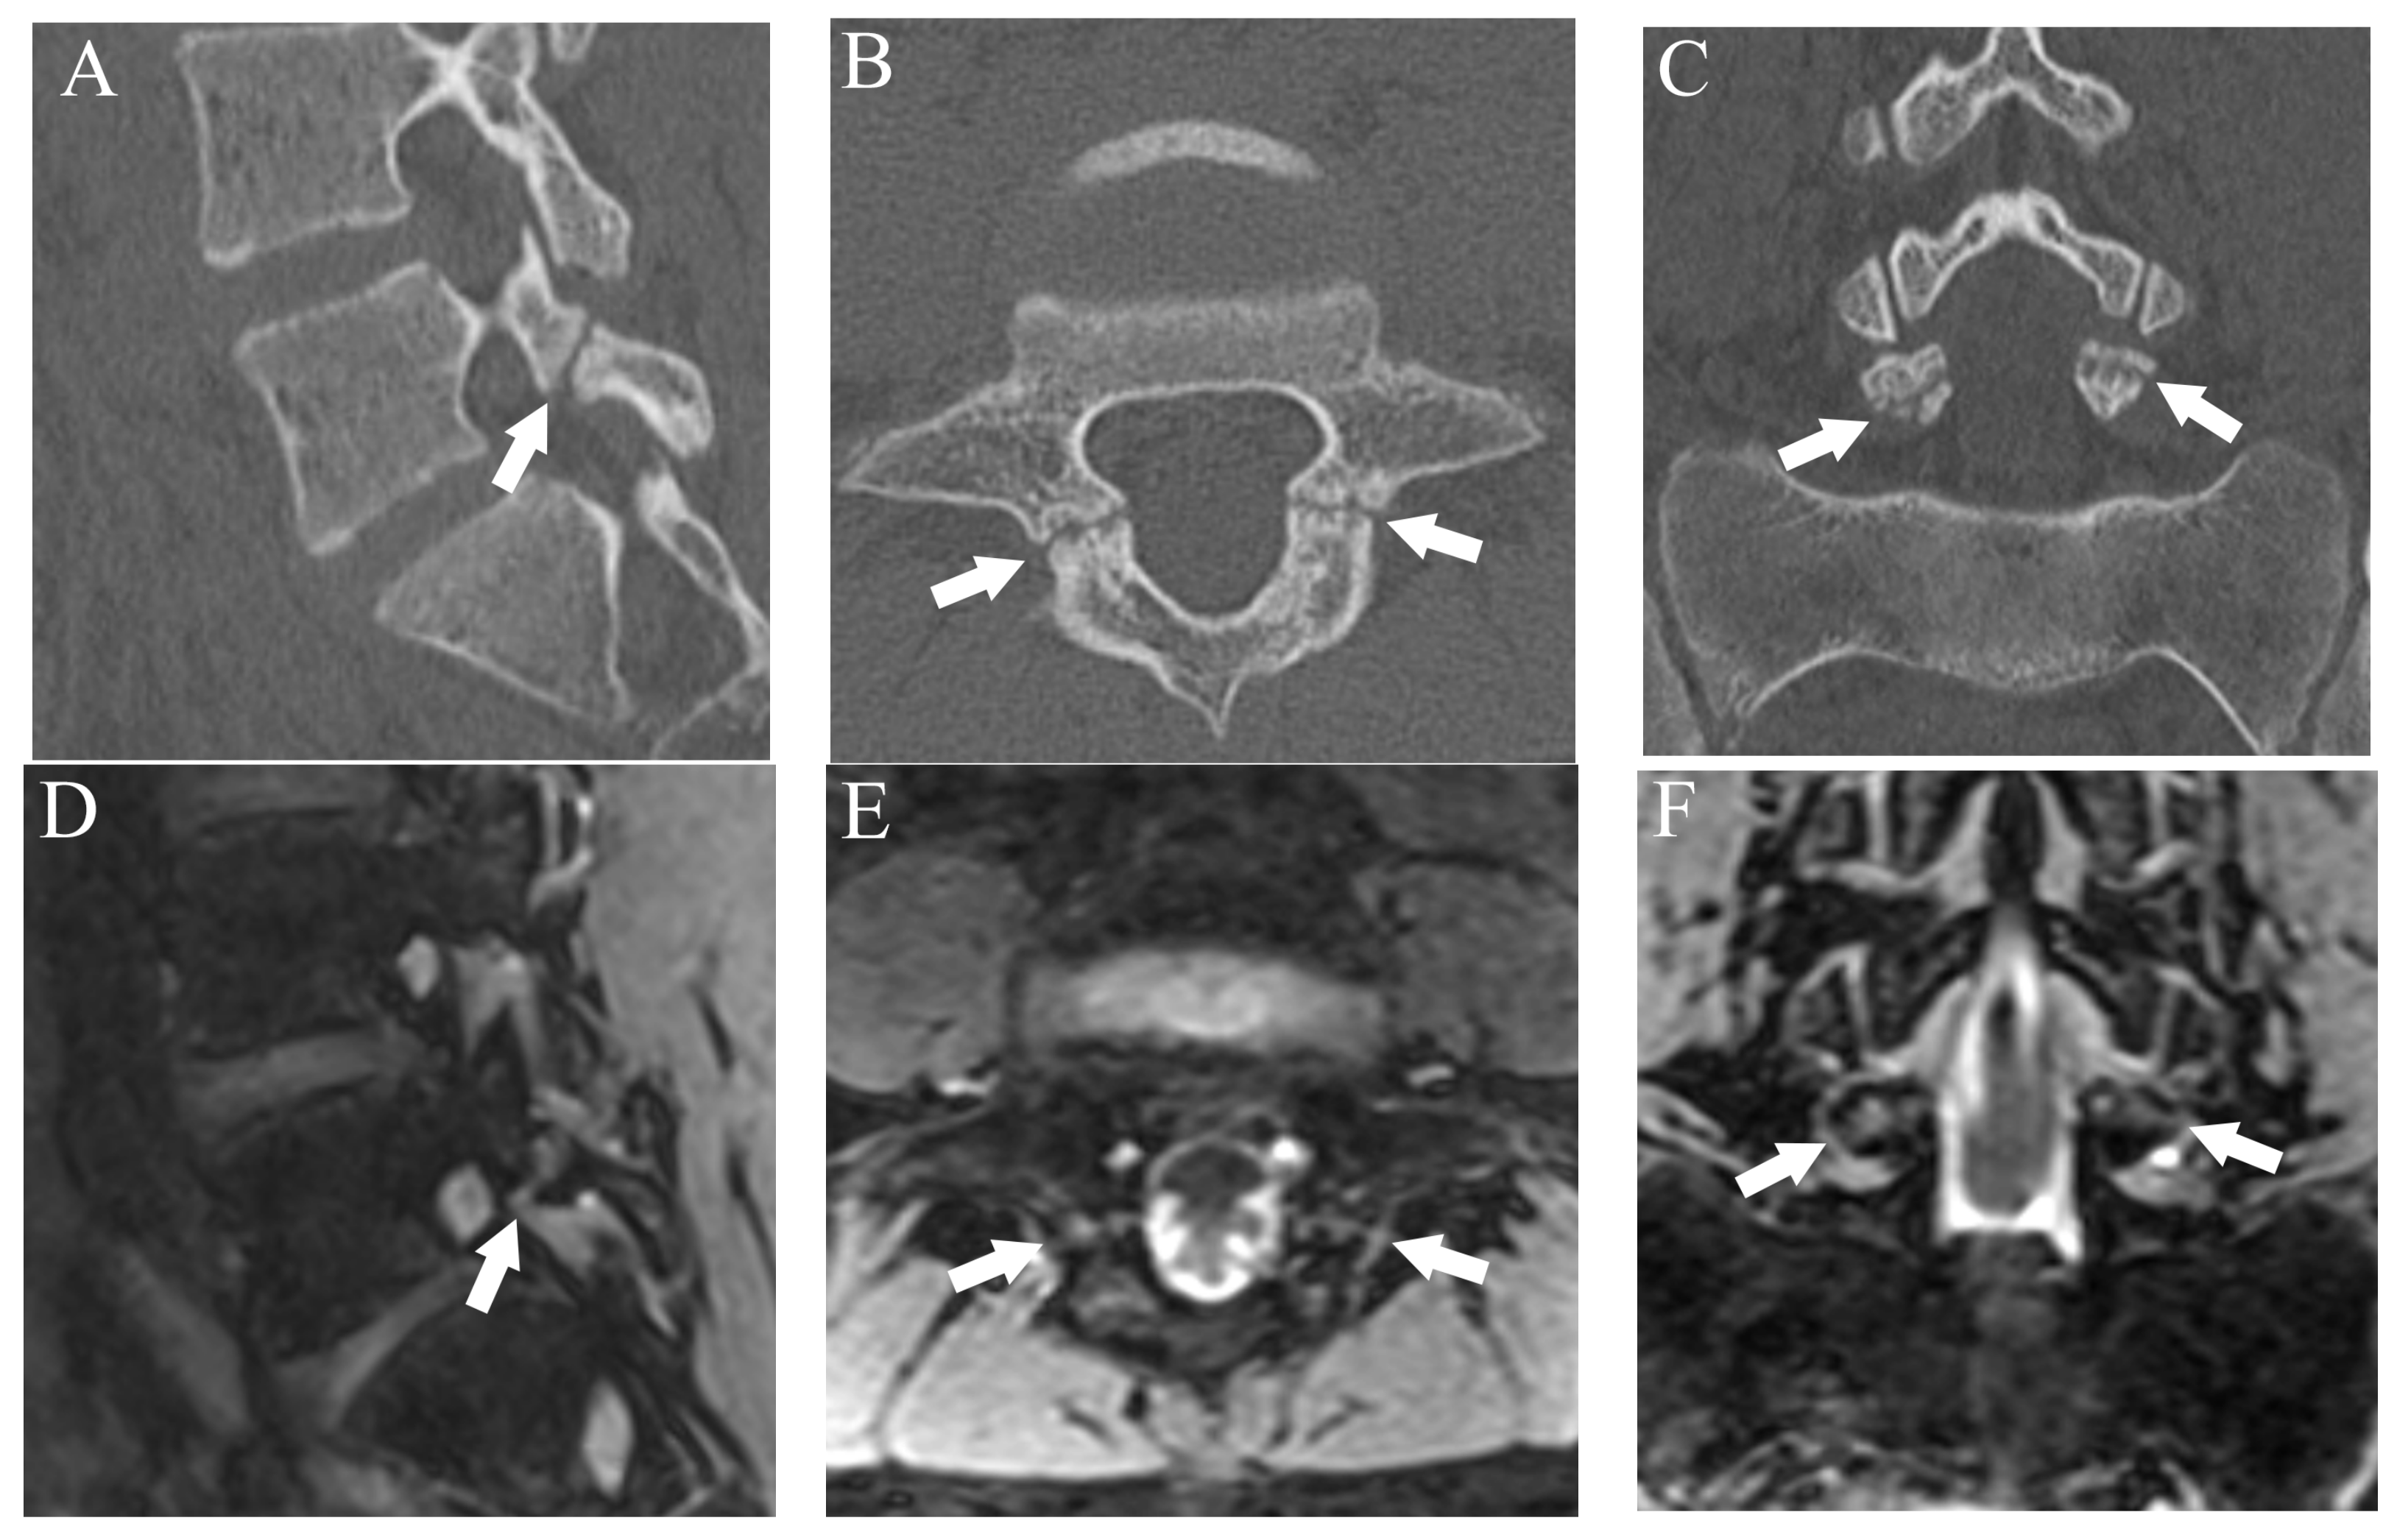

Figure 3.

Representative images of grade 3 fracture. The right pars interarticularis of L5 from a 16-year-old male. (A) Sagittal CT image showing a complete fracture across the whole pars interarticularis (arrow). (B) Sagittal DESS image showing a linear high signal corresponding to the complete fracture (arrow).

After more than a 2-week interval from creating standard references, two readers independently analyzed fractures on T1WI and DESS using the same grading system as used in CT. On MRI, bone resorption (grade 1) can be detected as slight hyperintensity within cortical bone which normally shows homogeneous hypointensity (Figure 1). The fracture line on MRI is delineated as linear hypointensity on T1WI and linear hyperintensity on DESS (Figure 2 and Figure 3). DESS was also used to evaluate the BME binary. Similar to STIR, if there is a high signal at pars interarticularis on DESS, it is considered positive for BME. Consensus results for T1WI, DESS for fracture and DESS for BME were created for statistical analysis.